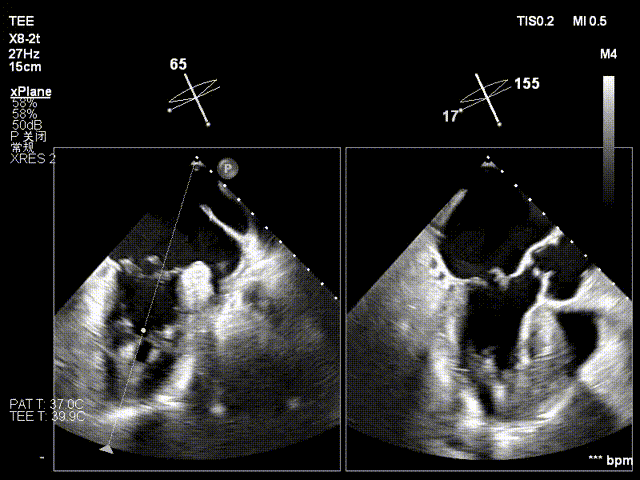

术前心超提示:

退行性二尖瓣反流(DMR),A2-A3脱垂伴连枷样运动(脱垂范围:17mm,连枷间距:7mm),P3脱垂,反流主要位于2-3区,MR重度4+(VC:6*17 mm),A3:18mm,P3:9mm,A2:24mm,P2:14mm,AP:32mm,二尖瓣口面积MVA约 5.6cm²,左房、左室明显扩大。

术中操作(关键步骤超声)

在全麻下,于心尖入路完成ValveClamp®装置植入。术中多学科团队密切配合,超声全程实时指导操作。最终,于2偏3区成功植入一枚Ⅲf夹子,一次夹合完成。前叶夹合量12mm,后叶夹合量10mm,反流降至1+,导管操作时间30分钟。术后平均跨瓣压差3mmHg。